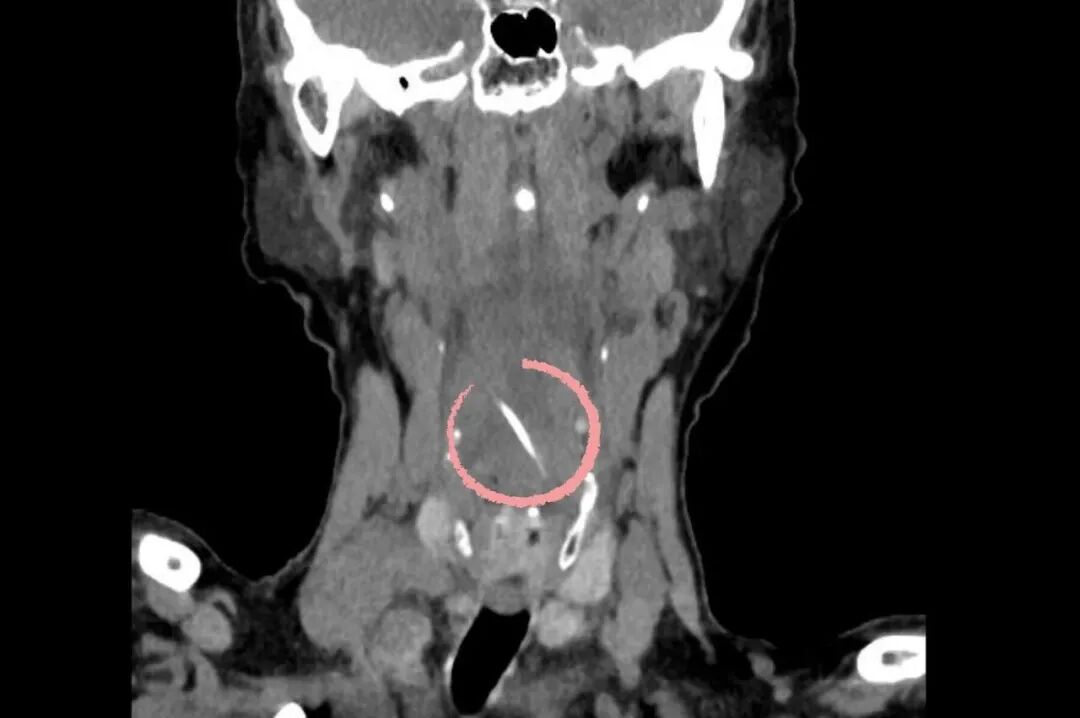

咽后壁中的鱼刺 医院供图